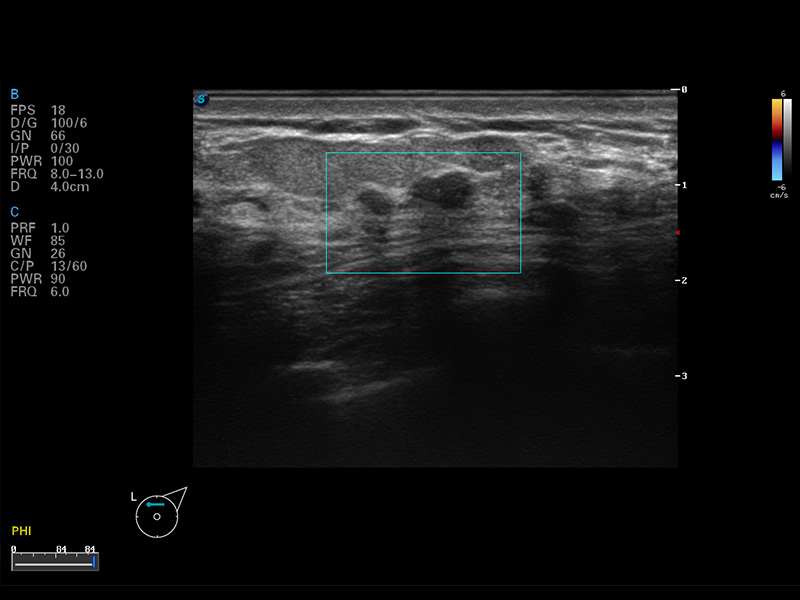

S8 EXP便携式彩色多普勒超声诊断仪是球速体育入口研发的高端全身应用型便携彩超。高通道的VIS平台融合可视化(Visual)、智能化(Intelligent)和人性化(Smart)的特点,配以球速体育入口自主研发生产的探头大家族,使您能够快速、准确的获得病人信息,提高工作效率的同时减轻疲劳。

成像技术

μ-Scan微米成像

谐波成像